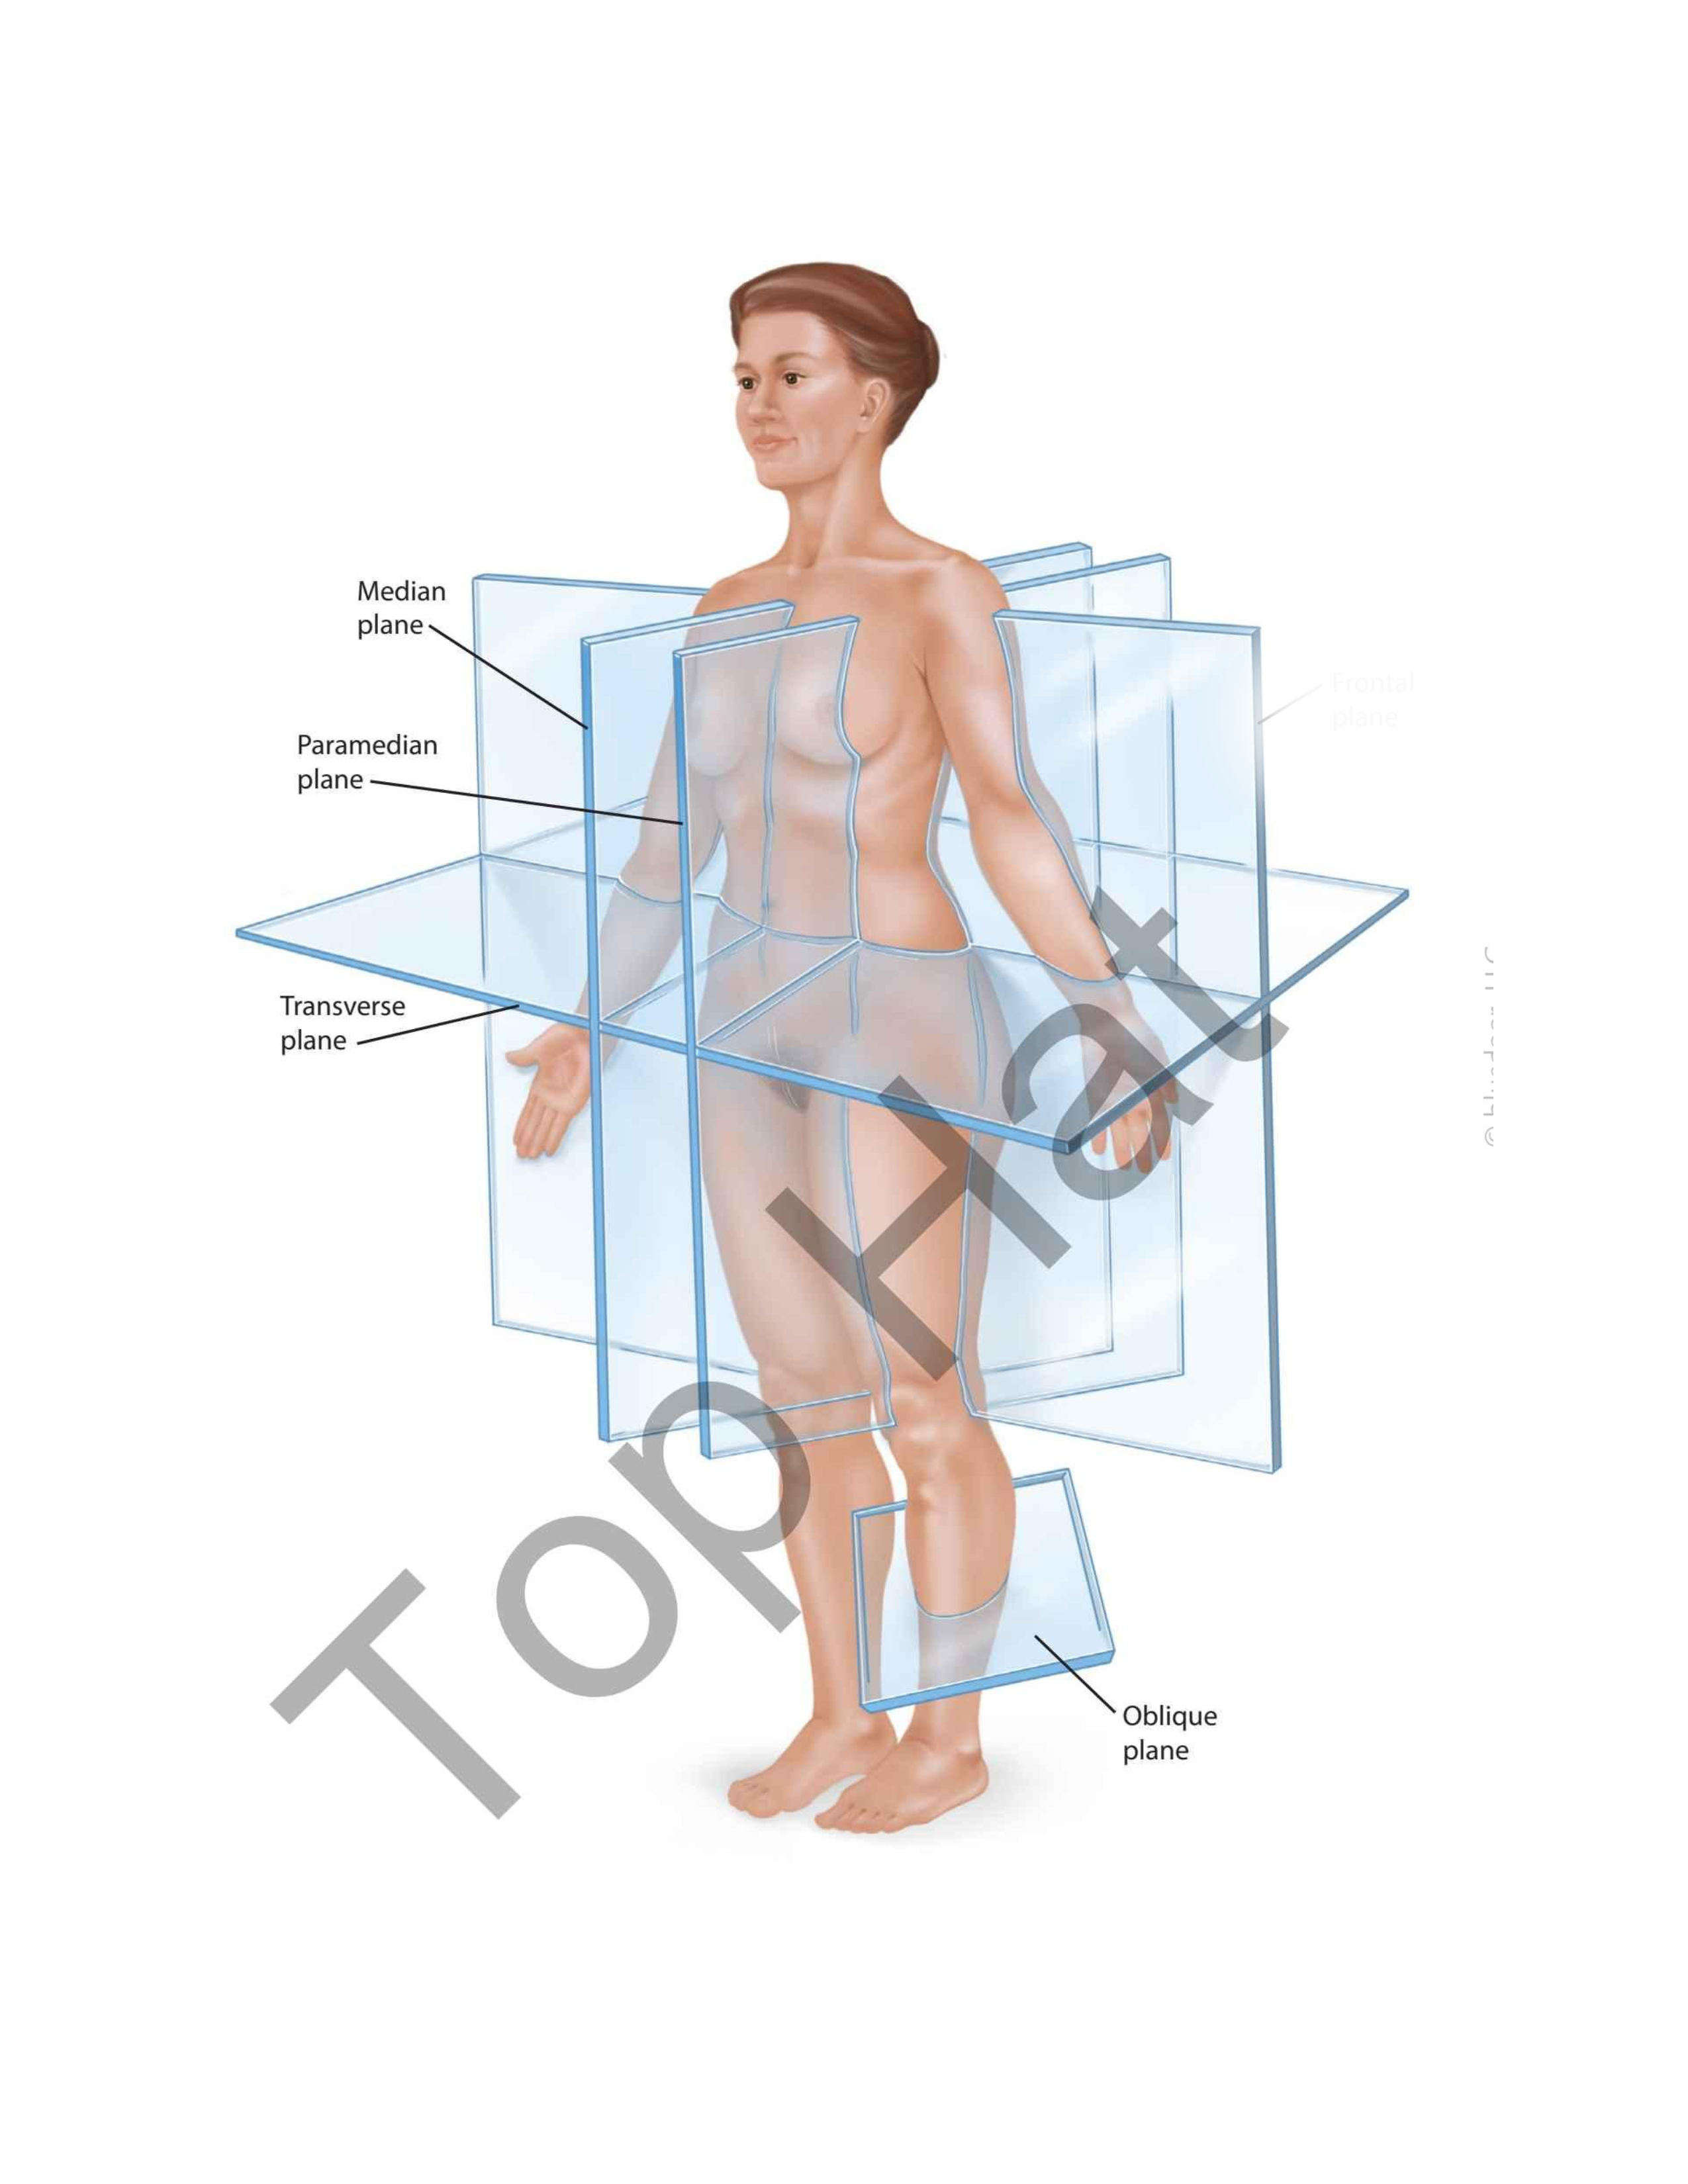

Median Plane

Oblique Plane

Transverse Plane

Paramedian Plane